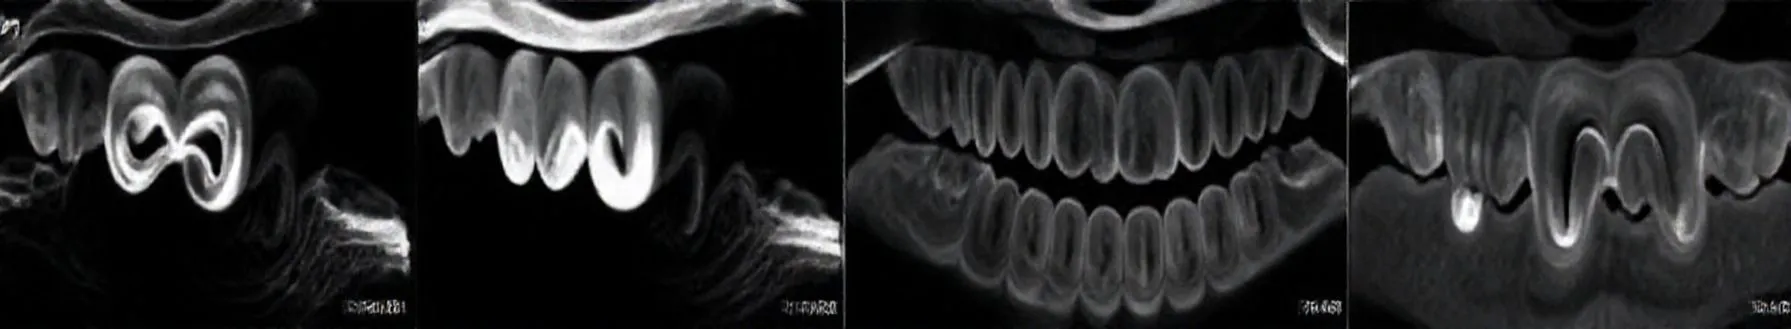

The use of CBCT in endodontics and this diagnostic technique is increasingly required in order to have a more accurate prognosis of the teeth to be treated.CBCT has great potential to become a valuable tool for diagnosing and managing endodontic problems, as well as for assessing root fractures,...

- CVCTs provide a three-dimensional view, crucial for inconclusive diagnoses, complex anatomy, retreatment cases, and assessing perforations or fractures. While 2D radiographs offer limited information, CVCTs enable better evaluation of root canal failures and anatomical variations, improving treatment predictability.